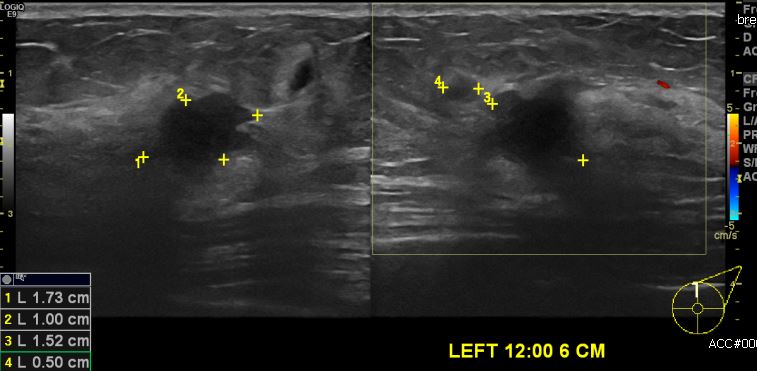

좌측 만져지는 멍우리로 내원하신 50대 여성분으로 좌측 12시 방향에 6cm 떨어진 거리의  의심스러운 혹 중심핵생검 시행하여 좌측 침윤성 유관암 진단 되었습니다.